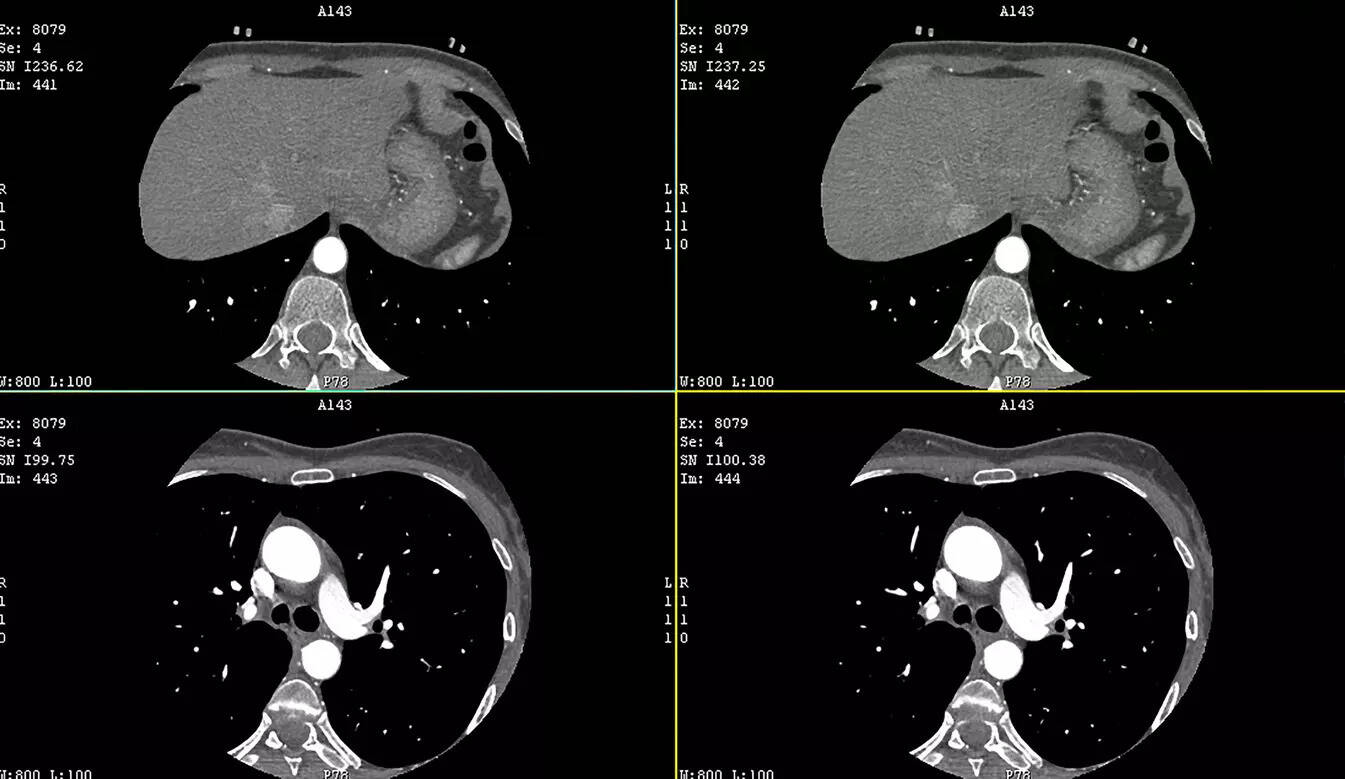

Emphasising that in younger patients coronary artery disease often presents suddenly without prior warning symptoms, Dr Chandra said, “Non invasive diagnostics such as CT coronary angiography, calcium scoring, stress imaging and biomarker assessment enable early risk stratification and timely intervention, significantly reducing long term myocardial damage.”

Attributing the sharp rise in calcium scoring largely to increasing awareness around preventive medicine, Dr Mahajan said, “CT based calcium scoring can predict future cardiac risk even before symptoms emerge, allowing clinicians to detect plaque burden and vascular changes at a pre symptomatic stage.”

Experts underlined that calcium scoring CT is particularly valuable in quantifying coronary artery calcification, an early indicator of atherosclerosis, enabling more accurate risk classification in asymptomatic individuals.